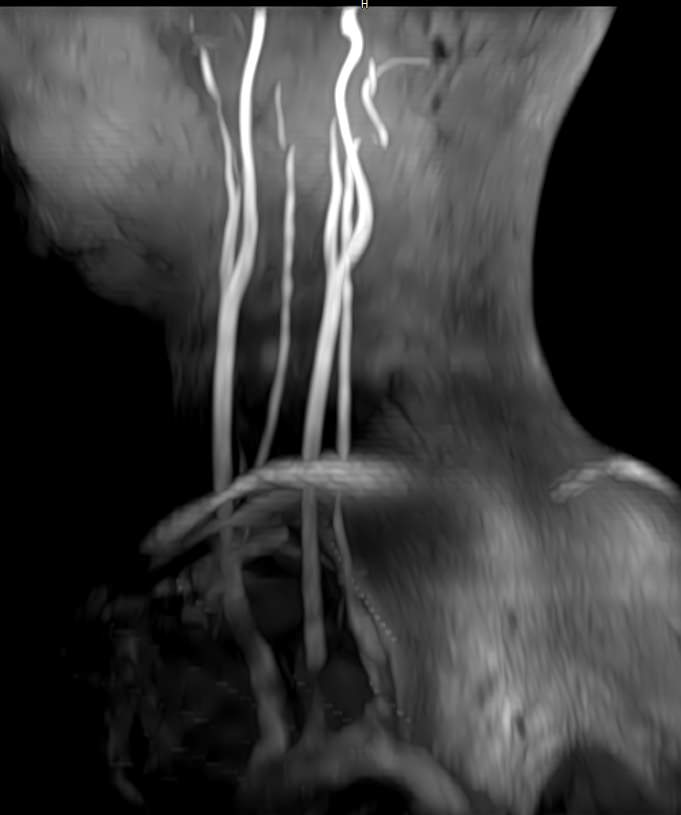

МР-артериография — неинвазивный безопасный метод исследования для диагностики патологии артериальной системы головного мозга. Магнитно-резонансная артериография позволяет получить трехмерное изображение сосудистой системы, кровоснабжающей центральную нервную систему, оценить анатомическое строение артерий головного мозга и функциональные особенности кровотока.

С помощью электромагнитных волн томограф послойно сканирует структуры исследуемого органа, затем посредством компьютерных программ преобразует полученные данные в трехмерное изображение. При этом на снимке видна только сосудистая система без окружающих тканей. Таким образом, сканирование в режиме ангиографии позволяет визуализировать артерии и вены головного мозга без контрастирования.